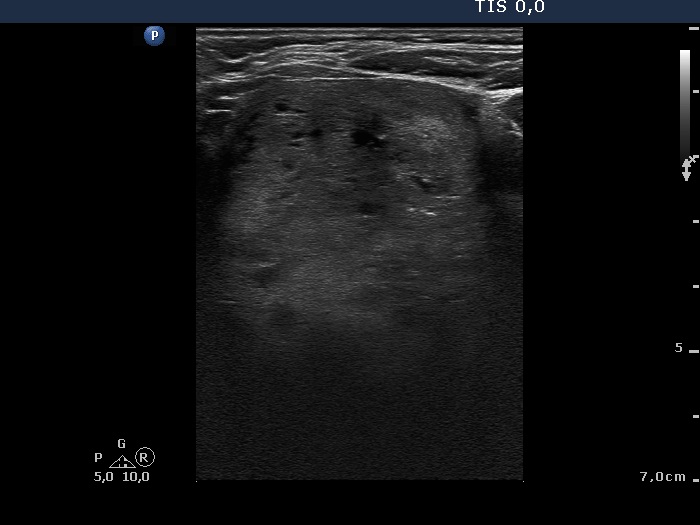

Benign hyperplastic nodules (histological diagnosis) - case cons 024 |

There are pale lines and granules within the nodule - these figures correspond to a connective tissue. The three granules are probably also presentations of a connective tissue.